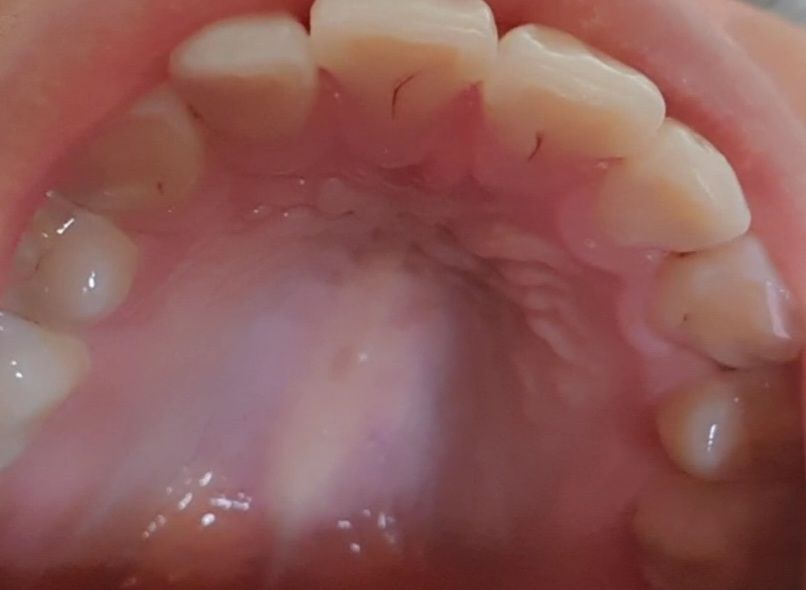

이정도면 치료가 시급한 수준의 충치인가요??

비용도 많이 드는 충치인지 너무 걱정돼서 올려봅니다ㅠㅠ 치아 사이도 어두운 부분이 보이는 것 같은데 저 정도면 충치가 많이 진행된 상태인가요?

앞니 안쪽에 표면에만 생긴 충치입니다. 이정도 충치는 치료하지 않고 조금더 지켜보다가 더 진행되면

치료해도 됩니다.

치아 사이에 있는 pit & groove에 생긴 충치로 이는 정확한 판단을 위해서는 방사선 사진 등을 찍어보셔야 합니다. 방사선 사진 상에서 생각보다 깊을 수 있습니다. 충치는 보통 삼각형 형태로 아래쪽이 넓어지기 때문에 보이는 부분보다 깊거나 넓을 수 있습니다.

따라서 이를 방치하게 되면 충치가 더 심해지거나 깊어질 수 있으므로 조기에 치료하는 것이 좋아 보입니다.

사진 상으로 완벽히 판단 할 수 없지만 사진 상으로만 판단할 때는 충치가 매우 깊은 것 같지는 않습니다.

사진으로 보는정도면, 충치이긴 하지만 충치가 아주 심해보이진 않습니다.

정지된 우식일 가능성도 있고, 불안하시다면 간단히 치료가 가능해보입니다.